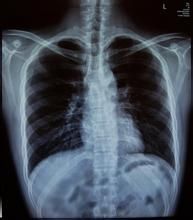

肺結核鈣化病灶鈣化是肺結核痊癒的形式之一,病變輕微、發現較早、治療及時的可以完全吸收,不在X光片上留下痕跡。

或只殘留一小疤痕病灶。多數成年人肺結核是以纖維組織增生所取代。X光片上表現為密度高的結節和條索狀影像,因此,病灶鈣化並不是肺結核痊癒的唯一形式。